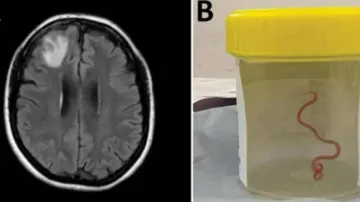

8-cm live worm removed from woman's brain in world's 1st discovery